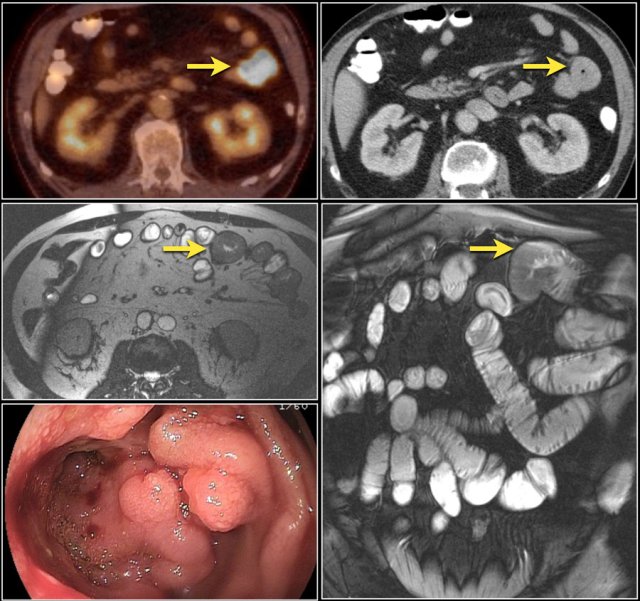

Top images show a circular mass in the proximal jejunum with FDG uptake (yellow arrows).

Lower MR-images show the same jejunal mass with shouldered borders and mesenteric lymphadenopathy (red arrows), consistent with adenocarcinoma.

The images show a short obstructing circular mass in the jejunum (yellow arrow) with enlarged lymph node (red arrow).

This proved to be an adenocarcinoma.

Post-contrast T1W-image with fatsat (left) and T2W-image (right) show an obstructing mass in the jejunum with shouldering (arrow).

There is prestenotic dilatation.